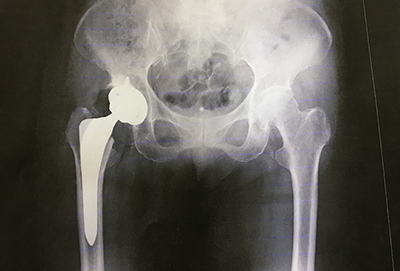

骨の変形が早い場合や症状が強い場合は、手術を行います。手術の方法には、自分の骨や関節を残す骨切り術と、股関節そのものを人工のものと取り替える人工関節置換術があります。

若い人を中心として、基本的には骨切り術を第一選択とすることが多いです。骨が死んだ範囲が大きい場合、骨が大きく壊れてしまった場合、また高齢者の場合は人工関節置換術を選択することが多いです。